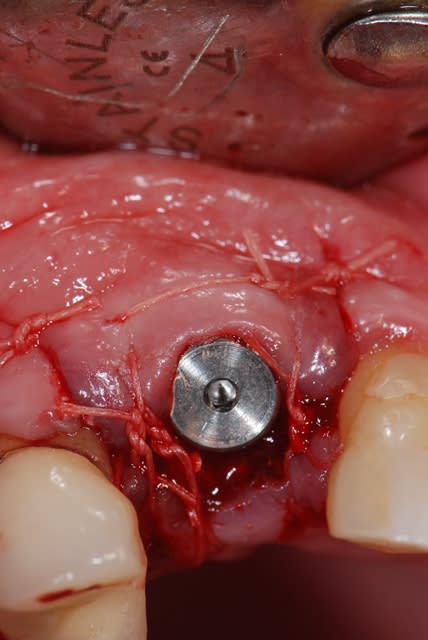

je te propose ce cas que j'ai achevé il y a 2 mois; tu verras que la notion de limite est variable, sauf celle du blocage primaire, d'où cette proposition de mise en esthétique uniquement avec un bon blocage primaire;

dans le cas présenté, je n'ai bien évidemment pas fait de mise en esthétique, j'ai simplement mis une PAP d'une dent, puisque la 14 est une CCM où je ne pouvais pas faire de collage

j'ai mis du ß TCP sans membrane, j'ai eu une très légère récession gingivale que l'utilisation des TBR Zircone autorise sans soucis avec un sourire non gingival

la pose a été faite 6 mois plus tard

Sutures bdm18l - Eugenol